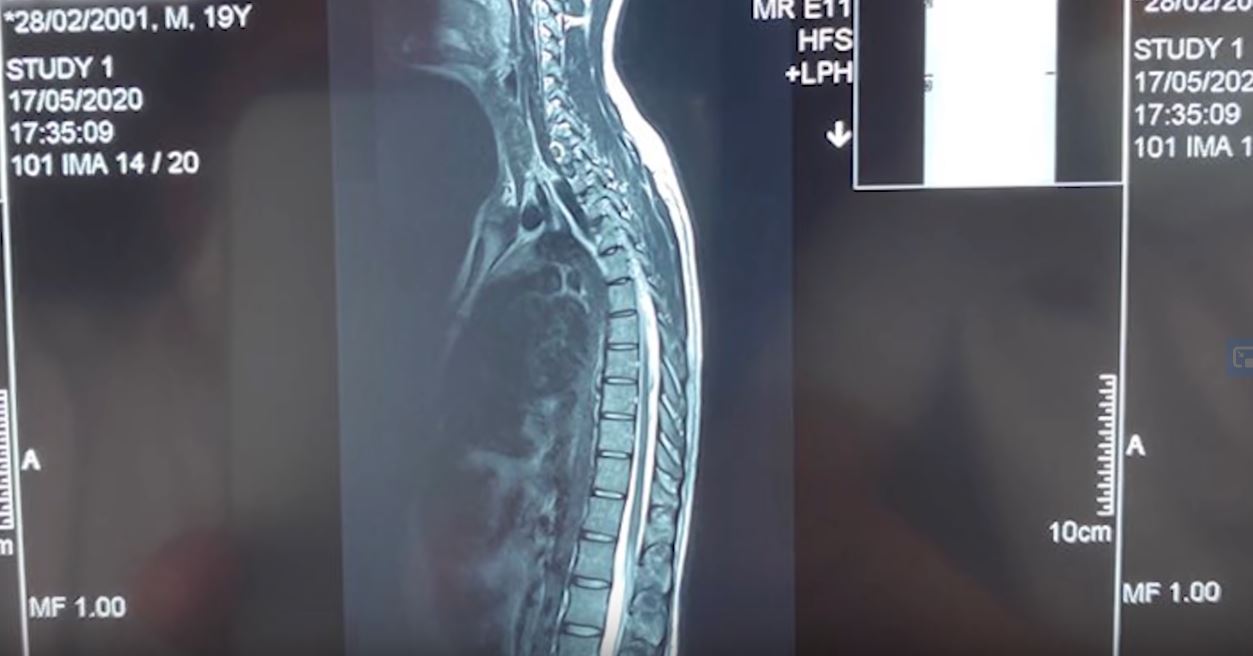

La doar 19 ani, vloggerul Selly a rămas paralizat timp de o oră, motiv pentru care a ajuns la spital. Tânărul și-a făcut un RMN și a aflat că suferă hernie de disc. Selly a povestit că durerea l-a lovit din senin, atunci când se plimba cu un prieten cu șalupa pe lacul Snagov. El pur și simplu nu s-a mai putut mișca timp de o oră, rămânând pur și simplu paralizat.

Selly a povestit că după ce a apelat la un prieten fizioterpeut, care i-a făcut o procedură care i-a relaxat temporar mușchii din zona lombară, a ajuns în cele din urmă la spital, acolo unde i s-a efectuat un RMN.

”Mulți m-ați îmtrebat de ce am fost la spital zilele astea, ați văzut la mine pe story. Nici eu nu știam cu ce afecțiune m-am dus acolo, știam că am o problemă la spate, m-am dus să-mi fac un RMN.